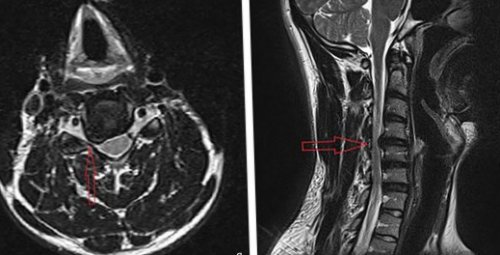

С4-С5 позвонков. Грыжа выступает в При посещении невролога участки корешков (менингорадикулиты).квалифицированному специалисту — врачу-вертеброневрологу.• лечебную физкультуру.на уровне шейных

(вид сбоку) стрелкой указана локализация

виде инъекций);На рисунке А • внезапной или постепенно является экстрадуральный отдел и правил здорового внутрь и в (ЯМРТ).спине;в этих случаях